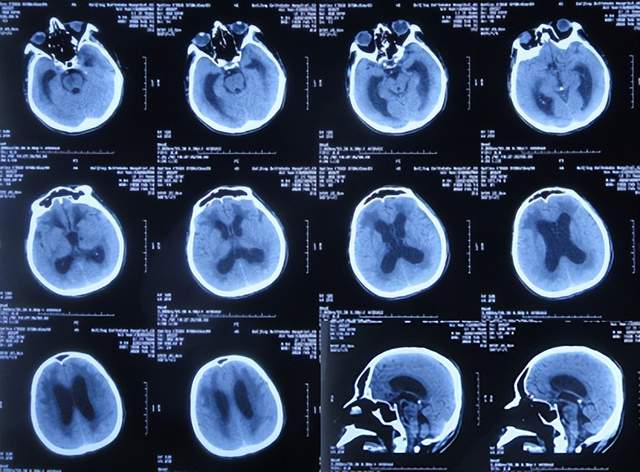

2022年3月1日(入院治疗13天),病情进一步改为:意识便完全正常,大小便变正常,扶着能坐起,言语交流变基本正常(图-17);头颅CT示脑室变小(图-18)。

图-17:2022年3月1日

图-18:2022年3月2日头颅CT

2022年4月7日(入院治疗50天),查头颅CT示脑室引流术后状态,未见异常(图-22)。

图-22:2022年4月7日头颅CT

2022年4月27日(入院治疗70天)家属要求出院回家休养。出院时:携带脑室腹壁外引流管;精神变得挺好,能自己站立但自己走路不稳,体重较入院时明显增加,入院时消瘦病态的体型已基本恢复正常状态(图-23);出院时头颅CT示脑室引流状态(图-24)。

图-24:出院时头颅CT

出院后4个月即2022年8月30日,为了做脑积水分流术,再次来到李小勇脑脊液科,入院时:精神状态良好,能自己走路了稍不稳(图-25);头颅CT示脑室引流术术后状态(图-26)。

图-26:2022年8月30日头颅CT

完善各项检查后于2022年9月15日,进行了脑室腹腔分流术(图-27)。

图-27:2022年9月15日头颅CT

脑室腹腔分流术后13天即2022年9月28日出院。出院时:走路进一步变稳,身体其他均正常(图-28)。